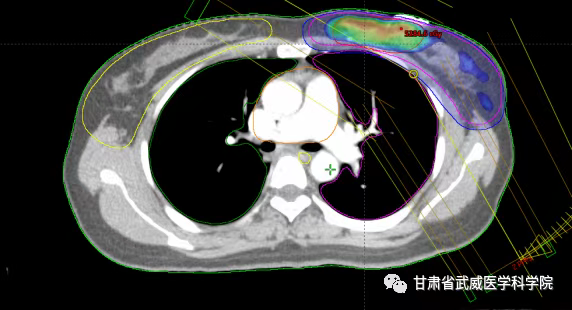

SIB-VMAT放疗计划

我院放疗五科胡廷朝副主任医师近几年开展了保乳术后的大分割放疗,目前已治疗病例20余例,瘤床给予39.5Gy,全乳43.5Gy采用VMAT同步推量技术,将之前的30次放疗时间缩短到15次,3周完成治疗,减少住院时间,几乎无严重并发症的发生,提高了患者术后放疗的依从性,节省了患者的治疗费用,受到了广大患者的好评及认可。此项技术的开展,为广大乳腺癌患者节省了治疗费用,带来了实惠,随着大分割放疗技术应用范围进一步得到拓展,未来预计越来越多的患者会从大分割全乳放疗中获益。使放射治疗进入一个更为“轻松”的时代。